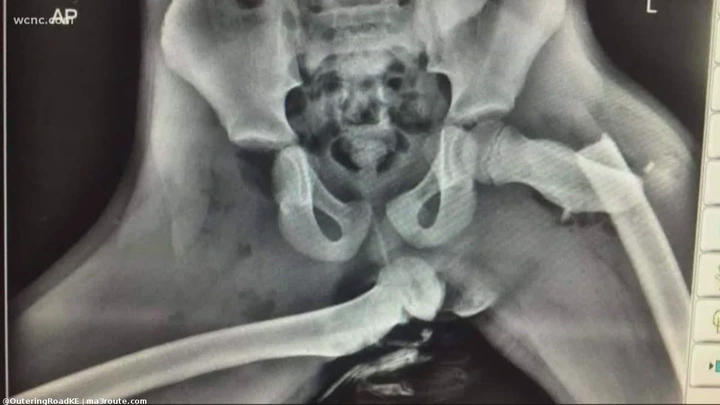

“The airbag went off, throwing my foot up and breaking my nose,” Janet explained. “I was looking at the bottom of my foot facing up at me.”

Janet’s ankle, femur and arm were all broken by the impact.

“Basically my whole right side was broken, and it’s simply because of my ignorance,” Janet said. “I’m not Superman. I couldn’t put my foot down in time.”